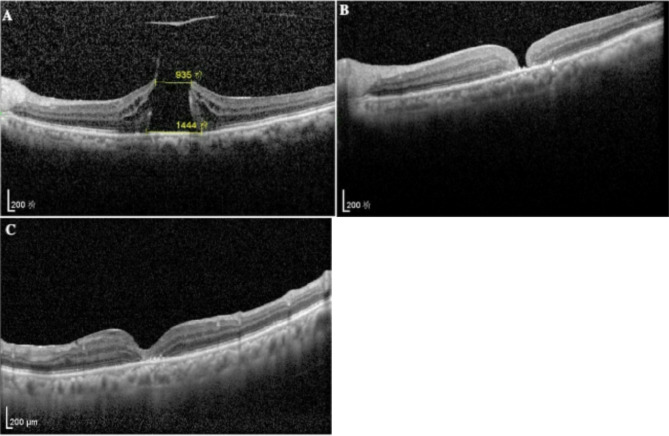

Background: Pars plana vitrectomy (PPV) combined with internal limiting membrane (ILM) peeling and sterilized air tamponade is used to treat macular hole(MH). Unsuccessful closure of the macular hole may occur after PPV, some caused by insufficient air tamponade or incorrect position. In-office air-liquid exchange may be an option for these patients.

Methods: A modified two-needle method of air-fluid exchange in office is introduced. A 29-gauge needle is inserted 3.5-mm posterior to the limbus at 6 o'clock. A second 29-gauge needle with a 5mL syringe filled with sterile air is inserted 3.5-mm posterior to the limbus in the superotemporal quadrant or superonasal quadrant. The plunger of the air-filled syringe is pushed while liquid of vitreous cavity flows out of the 6 o'clock needle drop by drop, and the flow rate of the fluid changes with the injection pressure.

Results: The method approximates the conditions of air-fluid exchange in vitrectomy, and the air injection and liquid outflow are balanced by pressure naturally.

Conclusion: The modified two-needle method is an easy, safe, and effective in-office air-fluid exchange for the treatment of unhealed macular holes.